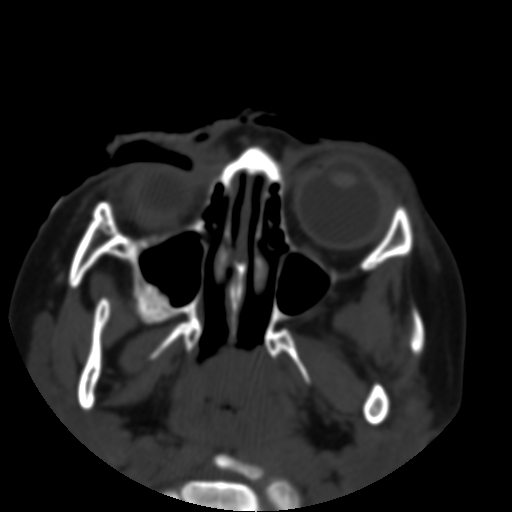

以下是引用深泽交通医院在2009-10-16 8:25:00的发言:[br]右眼环出血伴异物

以下是引用拾荒者在2009-10-17 18:38:00的发言:[br]鼻面部皮下积气,右侧睑缘及眼球壁高密度异物影,左侧眼球壁晶状体内侧缘处是圆形低密度影。低密度异物?应提请眼科医生注意。